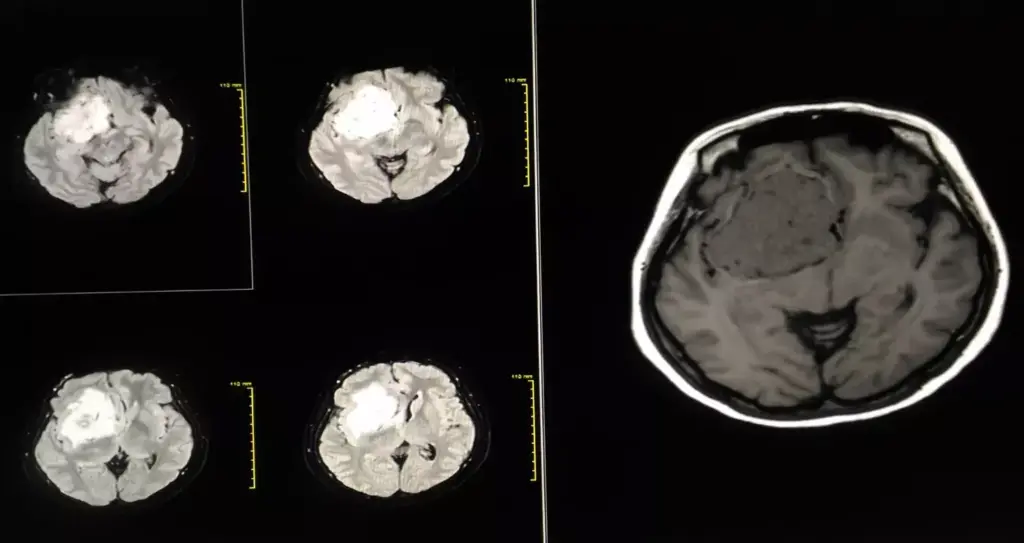

Imaging is key in finding brain tumors. We use different methods to see the tumor clearly. The main ones are MRI, CT scans, and PET scans.

| MRI (Magnetic Resonance Imaging) | Uses magnetic fields to create detailed images of the brain | High resolution, excellent soft tissue differentiation |

| CT (Computed Tomography) Scan | Uses X-rays to create cross-sectional images of the brain | Quick, widely available, good for detecting calcifications |

Then, we study the tumor’s location and how easy it is to reach. MRI and CT scans give us detailed info on the tumor’s size and position. This info is key for choosing the right surgery.